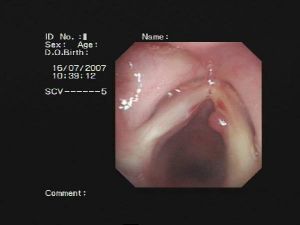

(2)喉鏡檢查:聲帶息肉多一側呈灰白色或淡紅色光滑的贅生物,有蒂或廣基或瀰漫性聲帶邊緣呈灰白臘腸狀腫塊。

喉癌(聲門型)多發生於老年男性,通常有長期吸菸史,聲嘶症狀為進行性加重。喉鏡檢查可見位於聲帶的菜花樣或結節狀腫物,表面不光滑或粗糙不平,可附著偽膜或有潰瘍形成,觸之質脆,較易出現,可向周圍組織浸潤,繼續發展可有聲帶固定。晚期可發生呼吸困難、轉移性頸淋巴結腫大,終末可出現惡液質等全身症狀。治療方法